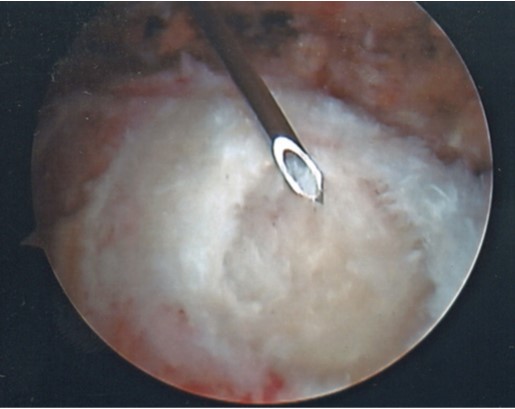

Desgarro del Manguito Rotador

El manguito de los rotadores esta constituido por 4 músculos que vienen de la escápula: Supraespinoso, Infraespinoso, Redondo menor y Subescapular. Los cuales son estabilizadores dinámicos de la articulación Glenohumeral.

Las lesiones del manguito de los rotadores son frecuentes y aumentan con la edad (desgarros degenerativos), pueden ocurrir como problema laboral por el movimiento repetitivo del miembro superior por encima de la cabeza, secundario a luxaciones de la articulación Gleno humeral.

Los desgarros dependiendo de sus características pueden ser tratados con fisioterapias, tratamiento quirúrgico artroscópico y en casos de ser irreparables se utilizan técnicas de trasferencia tendinosa o reemplazo articular.